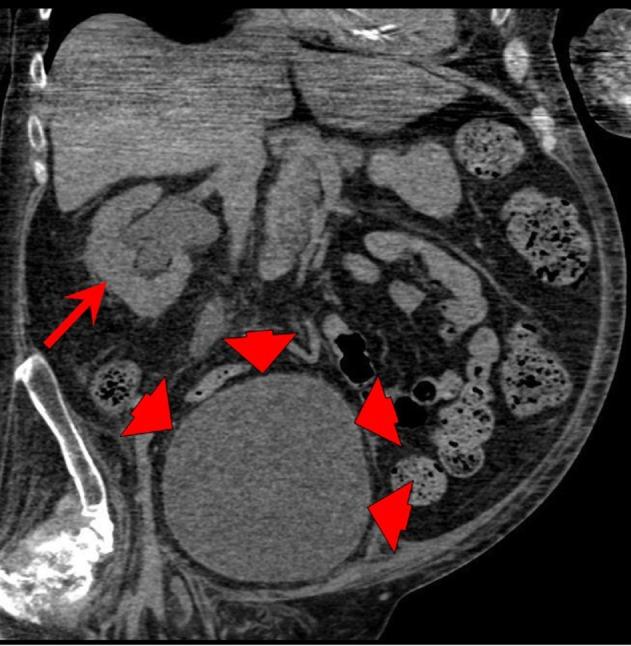

A male tetraplegic patient attended accident and emergency with a blocked catheter; on removing the catheter, he passed bloody urine. After three unsuccessful attempts were made to insert a catheter by nursing staff, a junior doctor inserted a three-way Foley catheter with a 30-mL balloon but inflated the balloon with 10 mL of water to commence the bladder irrigation. The creatinine level was mostly 19 µmol/L (range: 0-135 µmol/L) but increased to 46 µmol/L on day 7. Computerized tomography urogram revealed that the bilateral hydronephrosis with hydroureter was extended down to urinary bladder, the bladder was distended, prostatic urethra was dilated and filled with urine, and although the balloon of Foley catheter was not seen in the bladder, the tip of the catheter was seen lying in the urethra. Following the re-catheterization, the creatinine level decreased to 21 µmol/L. A follow-up ultrasound scan revealed no evidence of hydronephrosis in both kidneys. Flexible cystoscopy revealed inflamed bladder mucosa, catheter reaction, and tiny stones. There was no bladder tumor. This case report concludes that the cause of bilateral hydronephrosis, hydroureter, and distended bladder was inadequate drainage of urinary bladder as the Foley balloon that was under-filled slipped into the urethra resulting in an obstruction to urine flow. Urethral catheterization in tetraplegic patients should be performed by senior, experienced staff in order to avoid trauma and incorrect positioning. Tetraplegic subjects with decreased muscle mass have low creatinine level. Increase in creatinine level (>1.5 times the basal level) indicates acute kidney injury, although peak creatinine level may still be within laboratory reference range. While scanning the urinary tract of spinal cord injury patients with indwelling urinary catheter, if Foley balloon is not seen within the bladder, urethra should be scanned to locate the Foley balloon.

一名男性四肢瘫痪患者因导尿管堵塞前往急诊;拔除导尿管后,他排出了血尿。护理人员三次尝试插入导尿管均未成功,一名初级医生插入了一根带30毫升球囊的三腔Foley导尿管,但仅用10毫升水充盈球囊以开始膀胱冲洗。肌酐水平大多为19微摩尔/升(范围:0 - 135微摩尔/升),但在第7天升至46微摩尔/升。计算机断层扫描尿路造影显示双侧肾盂积水伴输尿管积水向下延伸至膀胱,膀胱扩张,前列腺尿道扩张并充满尿液,尽管在膀胱内未见Foley导尿管的球囊,但可见导尿管尖端位于尿道内。重新插管后,肌酐水平降至21微摩尔/升。后续超声扫描显示双肾无肾盂积水迹象。软性膀胱镜检查显示膀胱黏膜发炎、导管反应及微小结石。未发现膀胱肿瘤。本病例报告得出结论,双侧肾盂积水、输尿管积水及膀胱扩张的原因是膀胱引流不畅,因为未充分充盈的Foley球囊滑入尿道导致尿液流动受阻。四肢瘫痪患者的尿道插管应由资深、有经验的人员进行,以避免创伤和定位错误。肌肉量减少的四肢瘫痪患者肌酐水平较低。肌酐水平升高(>基础水平的1.5倍)表明急性肾损伤,尽管肌酐峰值水平可能仍在实验室参考范围内。在对留置导尿管的脊髓损伤患者进行尿路扫描时,如果在膀胱内未见Foley球囊,应扫描尿道以定位Foley球囊。